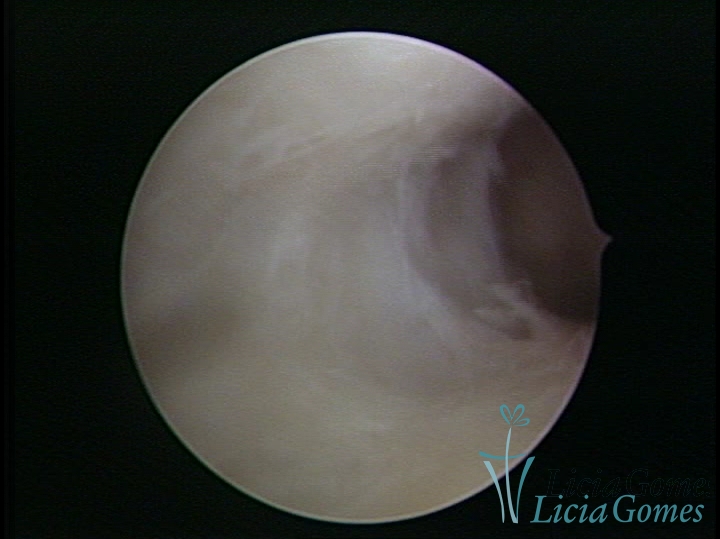

Sinéquia TIPO FIBROSA

• SINÉQUIA TIPO FIBROSA